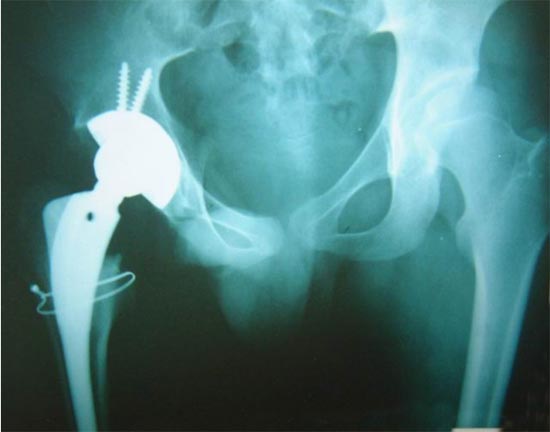

患者男性,52岁,左股骨颈骨折,曾经用空心钉和DHS固定,

两次手术均失败,股骨颈吸收,下肢短缩,疼痛,活动受限。

由于股骨近段两次手术均失败,导致股骨近段有骨质疏松骨缺损,

采用长柄的生物固定型股骨柄假体插入。

手术后X线片显示假体位置良好,双下肢恢复等长。患者功能恢复满意。